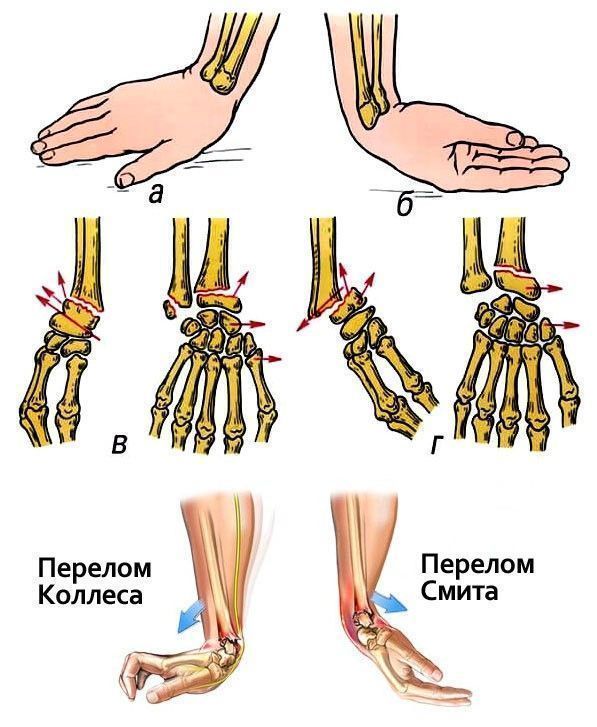

Изображения повреждения костей